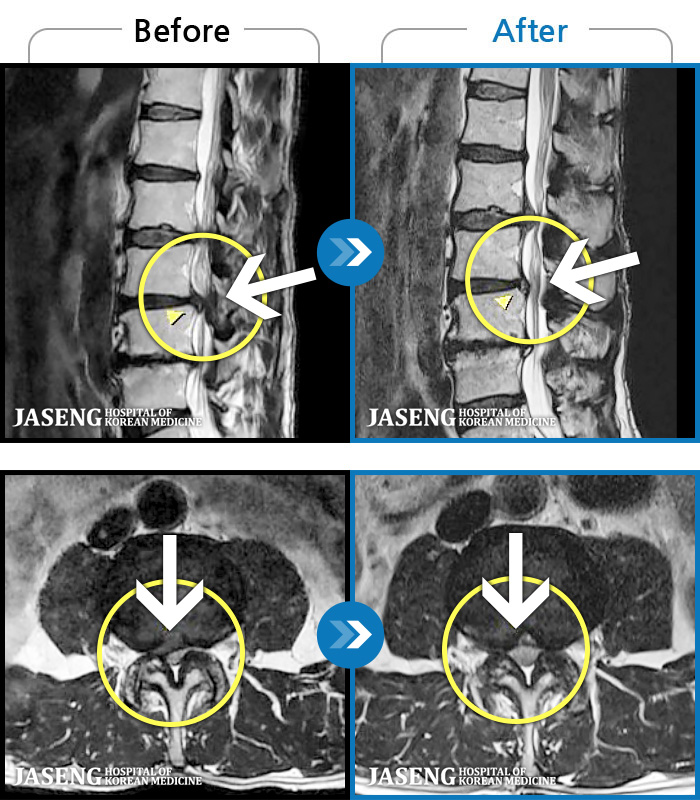

1,245 MRI ũ ʸ Ȯϼ.